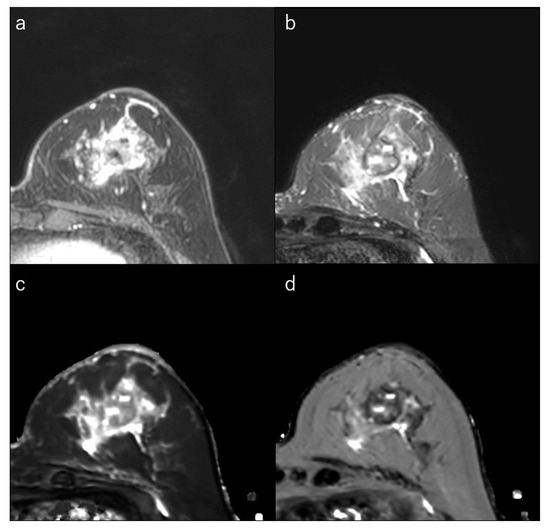

Figure 5.

(a) Dynamic contrast-enhanced MR image in a 56-year-old woman with human epidermal growth factor receptor 2-enriched breast cancer shows a round mass. (b) Short-tau inversion recovery image shows a high signal mass. (c) T1 map (window width/centre = 1400/2400 ms) shows a high signal mass; mean T1 of the mass is 1256 ms, (d) T2 map (window width/centre = 160/240 ms) shows an intermediate signal mass; and mean T2 of the mass is 88 ms.

HER2, a transmembrane receptor tyrosine kinase in the epidermal growth factor receptor family, is amplified or overexpressed in approximately 20% of breast cancers and is associated with poor prognosis, although it responds well to HER2-targeted therapies [4,6]. The cellular-level effects of HER2 overexpression include increased cell proliferation, cell survival, mobility, and invasiveness, as well as neo-angiogenesis by increasing VEGF production [6,7,8]. On gross pathology, a smooth mass margin was associated with the HER2-enriched subtype [32] (Figure 5). The presence of microcalcifications, especially branching or fine linear morphology, was associated with mammography [6]. HER2-enriched subtypes are more often associated with multicentric/multifocal disease than luminal-A cancers [32,156,157,160]. Increased angiogenesis in the HER2-enriched subtype leads to rapid early contrast uptake and a higher proportion of wash-out curves on DCE-MRI (Figure 2) [36].